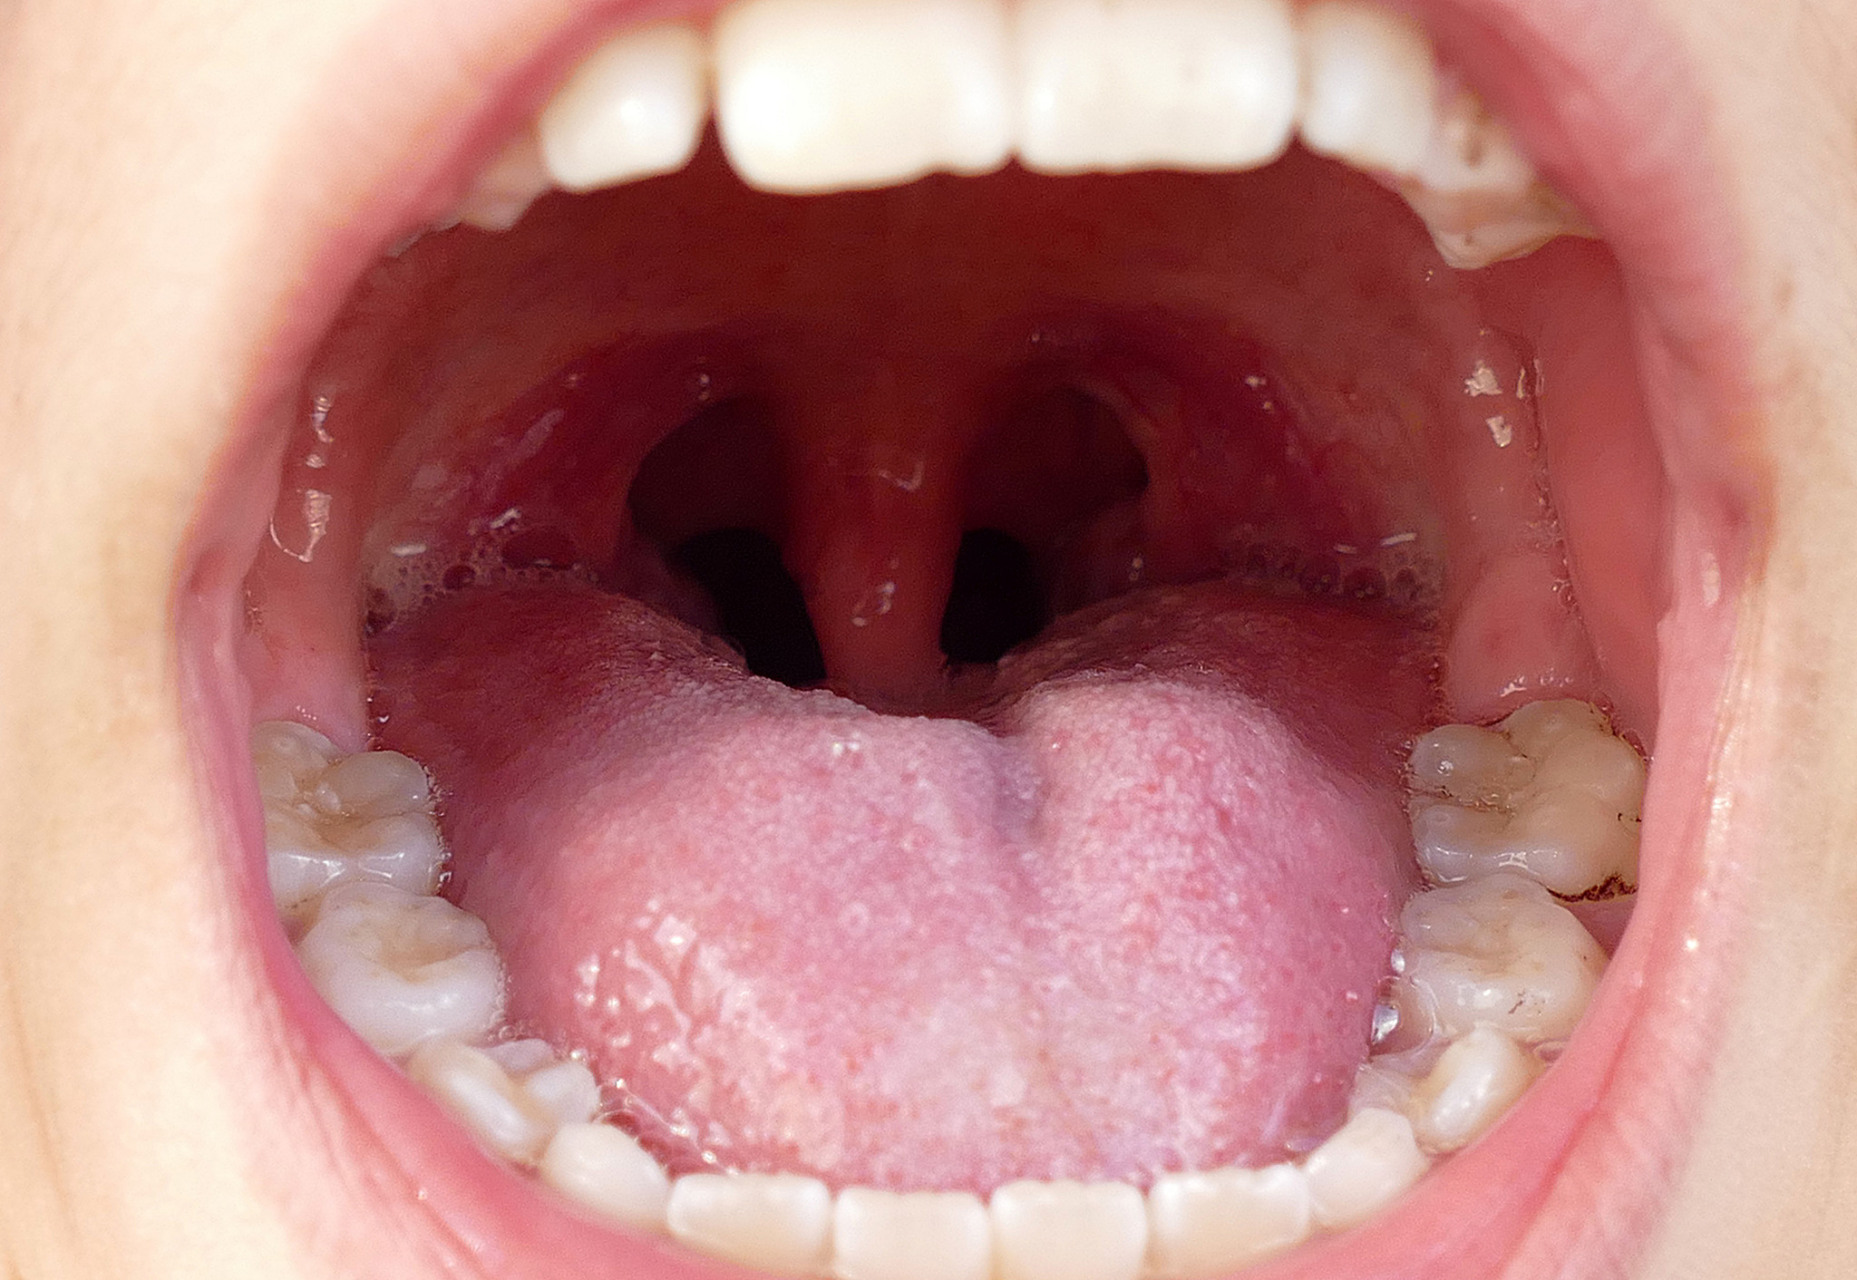

喉咙正常图片

图片尺寸480x640